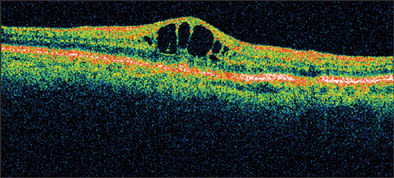

Clinically significant CME, by definition, is associated with a reduction in visual acuity. These patients usually have angiographic CME and obvious macular changes. Spaide and others have noted that clinically significant CME is most likely to occur in patients having complicated surgery and vitreous loss or implantation of an anterior-chamber intraocular lens (IOL).5 With the advent of new diagnostic instrumentation, even subtle changes in retinal thickness can now be detected (Figure 2). With the availability of advanced technology, including optical coherence tomography (OCT) and premium intraocular lenses, the expectations of both patients and clinicians have become significantly increased. McColgin and his colleagues reported that CME, defined as increased retinal thickness, occurred in 12% of patients following uncomplicated cataract surgery.20 It should be noted that while most patients with pseudophakic CME do not have quantitative reduction in their visual acuity, many patients do complain of persistent reduced contrast sensitivity and color desaturation, despite treatment and normal recorded Snellen vision.

IMAGE APPEARS COURTESY OF KING Y. LEE, MD.

Figure 2. CME as indicated on Heidelberg OCT.